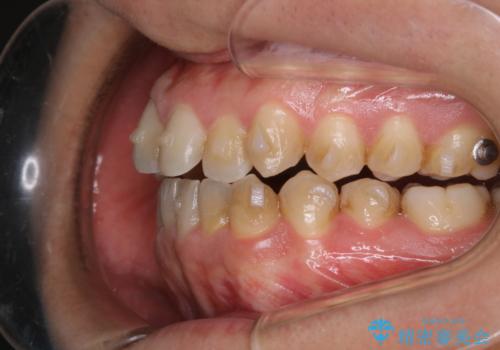

インビザラインで矯正治療中のクリーニング(PMTC)

- 全体的にクリーニングしてほしいとのことで来院されました。

PMTC60分コースを行いました。

インビザラインでの矯正治療は、歯の表面にアタッチメントといって白い突起を付けますので、材料の質的にも普段よりも汚れがかなり付着します。着色も付きやすいです。

虫歯や歯周病が進行しないように定期的にクリーニングすることをおすすめします。インビザライン経過のチェックが2、3ヶ月に1回のためそのくらいのペースで一緒にクリーニング行うことが最適です。